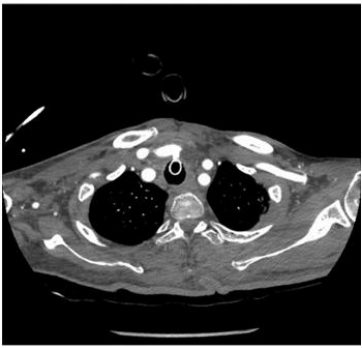

Fig 2

Imaging Findings

Emergency multiphasic CT carotid angiography using IV contrast was performed, including axial thin cuts with multiplanar and maximum intensity projection (MIP) reformatted images.

The study revealed:

• Abnormal fistulous communication between the brachiocephalic artery and the upper anterior tracheal wall, approximately 3 cm below the cricoid cartilage.

• The fistula measured approximately 5 mm in length.

• Dense secretions were noted in the trachea and main bronchi.

• Diffuse marked atherosclerotic changes were observed in the visualized portion of the thoracic aorta, characterized by mural irregularities, thickening, and intimal calcifications.

• Mild atherosclerotic changes were noted in the bilateral common carotid arteries and the extracranial segments of the internal carotid arteries, with no evidence of significant stenosis.

Figure 2